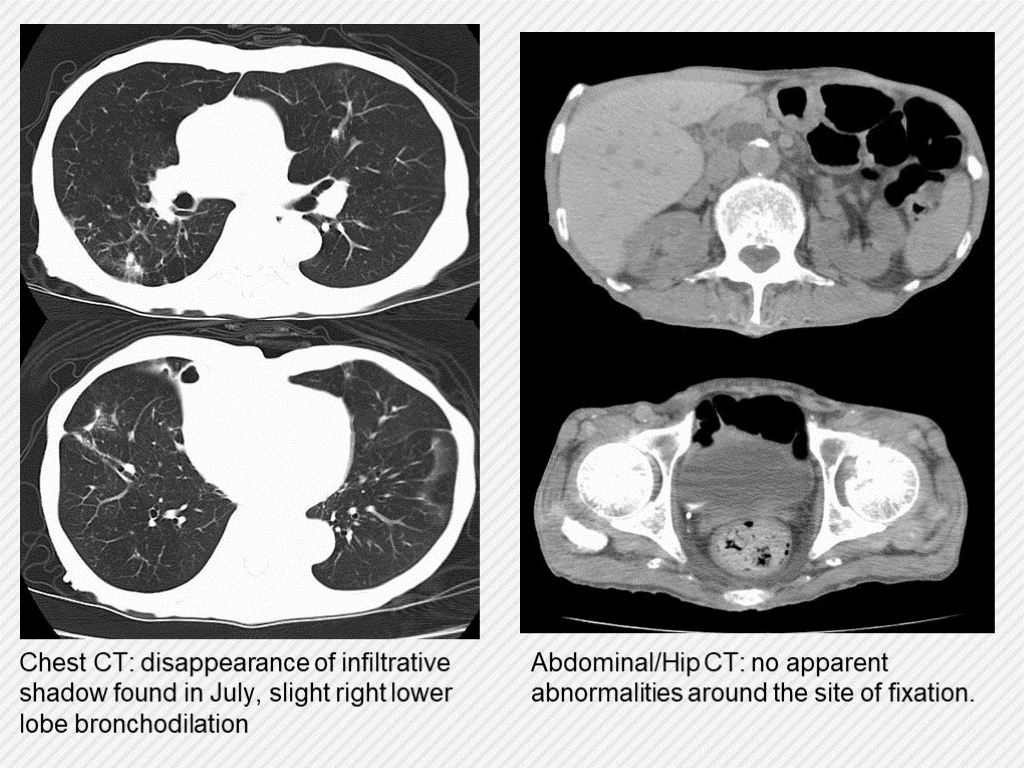

Chest CT: disappearance of infiltrative shadow found in July, slight right lower lobe bronchodilation Abdominal/Hip CT: no apparent abnormalities around the site of fixation.

#12.